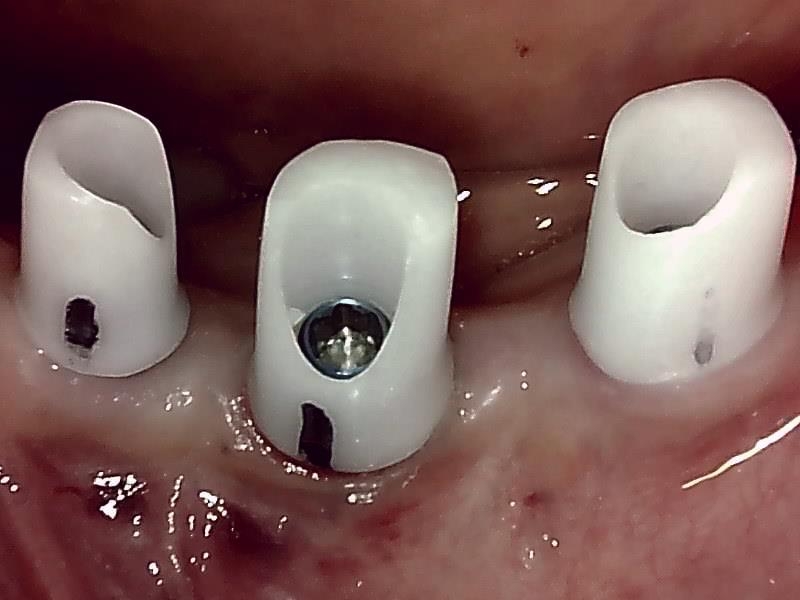

歯肉の整形 (左下)とても綺麗な良い歯肉の状態です。

アバットメント装着 (左下)

(ジルコニアアバットメント)

(ジルコニアアバットメント) (咬合面観)